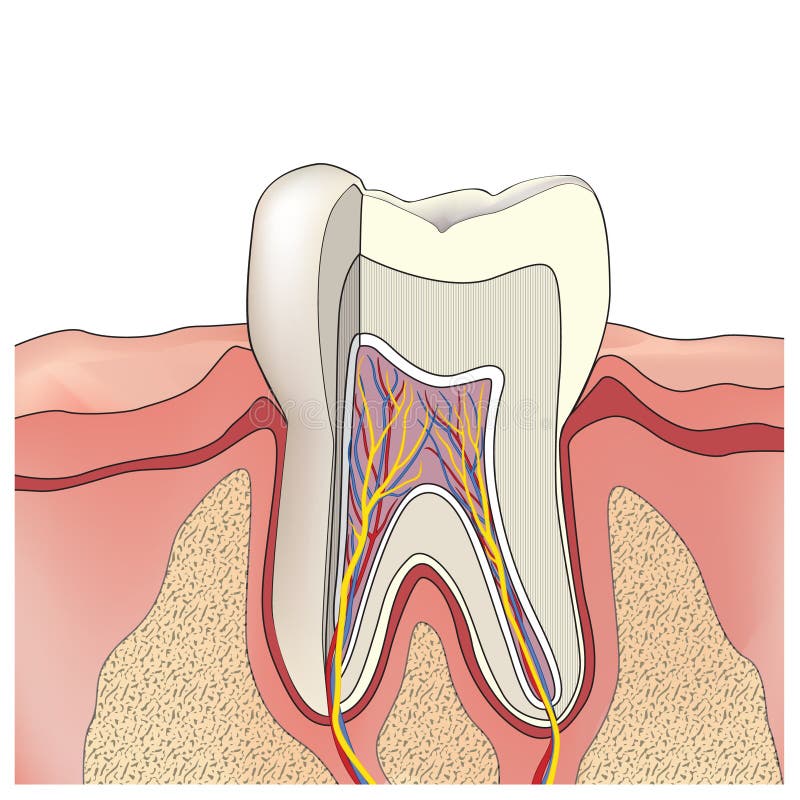

Tanden strukturerar Medicinskt diagram av strukturen av det inre tvärsnittet av tanden